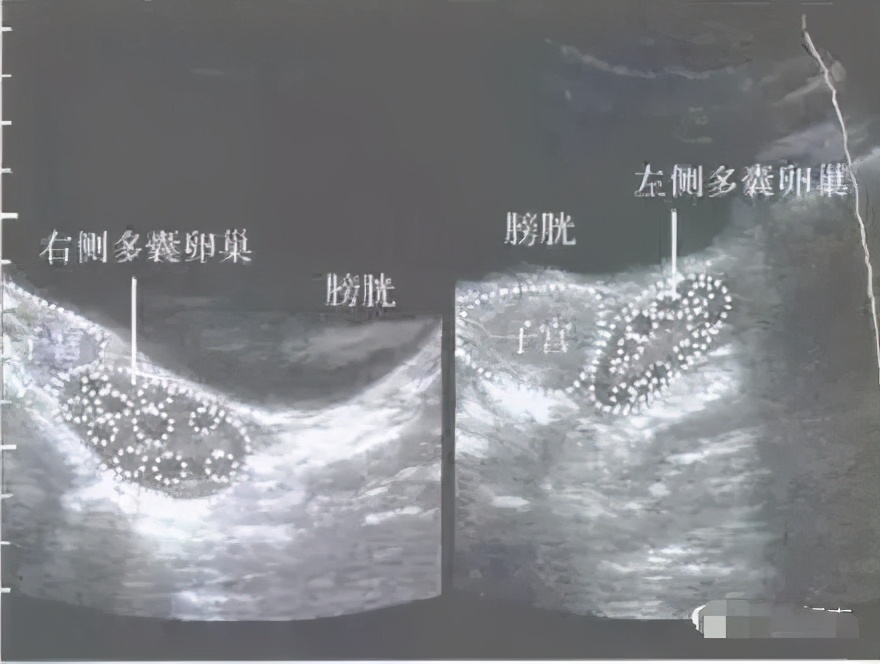

①B超检查提示双侧卵巢上小卵泡分别≥12个;

卵巢多囊样,英文缩写是PCO,和多囊卵巢综合征PCOS 少了一个字母,但这意思可大有不同。卵巢多囊样PCO是一种超声下观察到的状态,有比较多的小卵泡,可以是单侧,也可以是双侧。

多囊卵巢综合征PCOS是一种复杂的内分泌紊乱综合征,主要以不规则排卵或者不排卵,高雄激素为特征,会有多种症状,而不仅仅是卵巢多囊。而卵巢多囊样PCO,是多囊卵巢综合征可能的表现形式之一,但不是必须有的。

也就是说,多囊卵巢综合征可能卵巢多囊样,也可能没有,卵巢是动态的。卵巢多囊样不能用于确诊多囊卵巢综合征,它不是金标准,不是说只要PCO就是多囊卵巢综合征PCOS了。